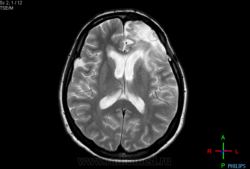

Женщина, 1967 гр, после оперативного вмешательства в левой лобной доле (удаление глиобластомы/ан. олигодендроглиомы-различные данные гистологии), операция в мае 2011, в карте есть МРТ от дек 2011- нет данных за продолженный рост, май 2012 -доктор пишет- объемное образование правой височной доли (кистозно-солидное). Пришла по направлению от онколога, исключить метастаз глибластомы , и продолженный рост в левой лобной доле. Доктора. нужен совет на счет правой височной доли....

с контрастом, накопления не вывялено

арахноидальная киста справа.... послеоперационные кистозно-глиозные изменения слева...

Признаков продолженного роста нет. Также соглашусь с мнением об арахноидальной кисте справа, и послеоперационных изменения в левой лобной доле.

я так и написала в заключении, спасибо вам, закрались сомнения тк предыдущий доктор отметил это как объемное образование. В интернете нашла информацию о том . что в случае послеоперационного слипчивого арахноидита на противоположной стороне происходит расширение ликворных пространств...